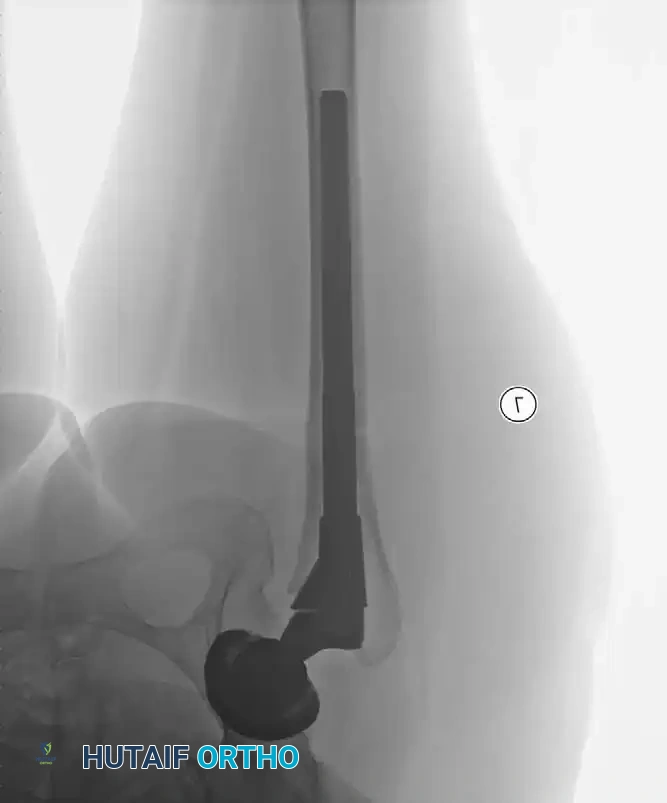

Radiographic Case Examples: Osteoarthritis and Complex Reconstructions

The following imaging series demonstrates various stages of complex acetabular and femoral preparation, highlighting the necessity of restoring offset and center of rotation.

Radiographic Case Examples: Osteonecrosis and Complex Femoral Reconstructions

Final seating of a cementless femoral stem in optimal neutral alignment.

Postoperative radiograph confirming excellent fit and fill of the femoral component.

Associated Surgical & Radiographic Imaging

Hutaifortho's Orthopaedic Diagram